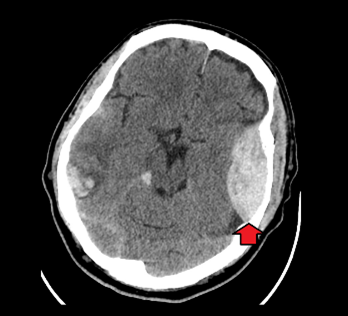

CT Scan không cản quang

: tiêu chuẩn vàng (gold standard).

→ Hình ảnh

khối tăng đậm độ, dạng thấu kính hai mặt lồi (biconvex)

, không vượt qua đường khớp sọ.